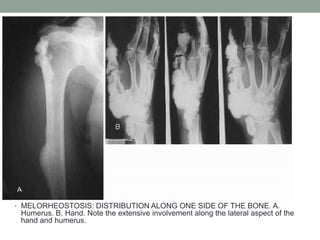

• MELORHEOSTOSIS: DISTRIBUTION ALONG ONE SIDE OF THE BONE. A.

Humerus. B. Hand. Note the extensive involvement along the lateral aspect of the

hand and humerus.

• MELORHEOSTOSIS: DISTRIBUTIONALONG ONE SIDE OF THE BONE. A. Humerus. B. Hand. Note the extensive involvement along the lateral aspect of the hand and humerus.